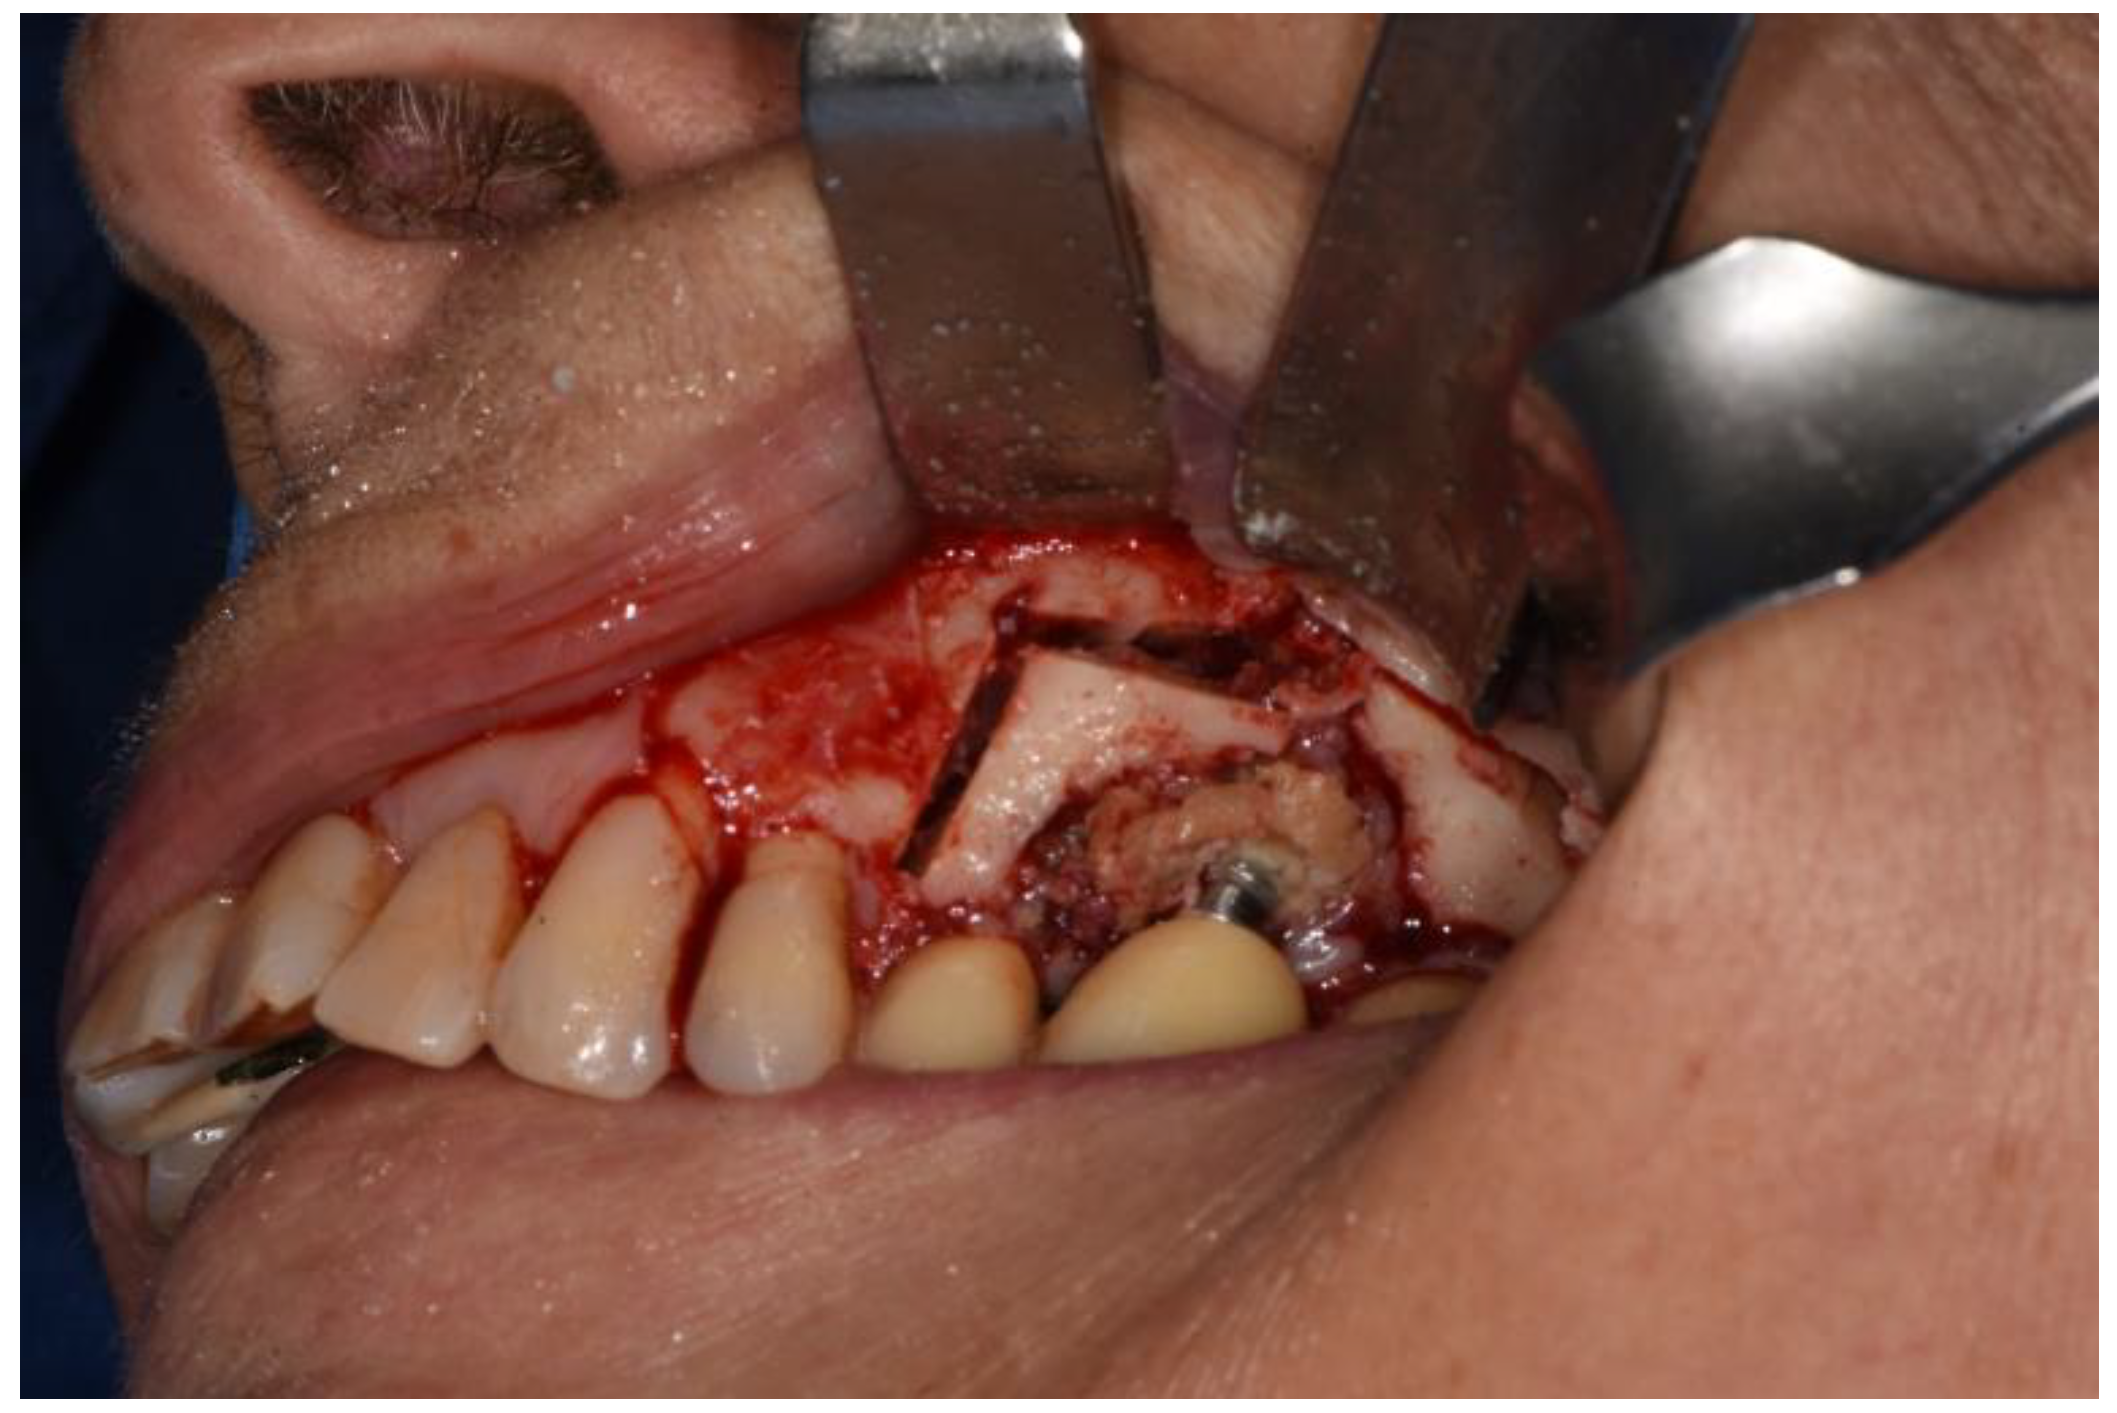

Figure 4. Osteotomy with piezoelectric device.

Surgeries 02 00040 g004

Figure 5. Osteotomy completed polipoid tissue in the maxillary sinus.